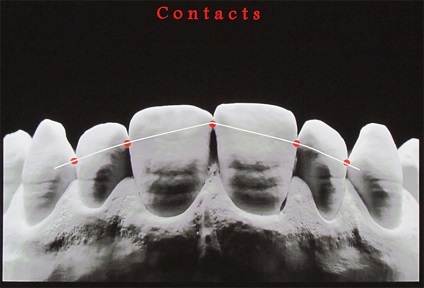

A frontális profilja az érintkező felületek az elülső fogak S-alakú, amely egy konvex rész és a konkáv rész.

A domború részét az érintkező felületek szintjén a legnagyobb szélessége a koronát képez két homlokegyenest kapcsolattartó pontok találhatók különböző magasságban. Két szomszédos érintkezési pontja két szomszédos fogak tartalmazhat egy kapcsolattartó pont, amelynek területe egyenlő a kb I mm-elülső fogak.

Annak ellenére, hogy két szomszédos korona szemközti fogak különböző magasságú, a vele érintkező pont az érintkező felületek találhatók ugyanazon a szinten. Ez az eljárás biztosítja a fogazat különböző konvex medialis és laterális / távoli felületek. Fang, kivételt képeznek az egymást követő csökkenése a magassága a fogak korona, az integráció a fogsor által nyújtott speciális formája. Másrészt, a különböző domborulata az érintkező felületek a fogak vezet az a tény, hogy a korona a felső metszőfogak helyzetben laterális és mediális kapcsolattartó pontok különbözik függőlegesen körülbelül I mm oldalsó felületén - közelebb a nyakát a fogak, a mediális felszínén - közelebb áll az élvonalbeli .

Ennek eredményeként, az érintkezési pontok az elülső felső fogak vannak elrendezve egy ív, megismételve a helyzetben a vágóélek vagy meghajlítjuk a felső széle az alsó ajak. Az alábbiakban, mind a felső fogazat a kapcsolattartó pont a kettő között metszőfogak.

A kapcsolattartó pontok között, a felső elülső fogak elrendezve egy görbe mentén, megismételve a hajlam a vágóélek a felső és alsó ajak kontúr. Ha az érintkezési pont között a metszőfogak és a szemfogak vetített középvonalában, akkor hogy három szinten egy pályát körülbelül 1 mm.